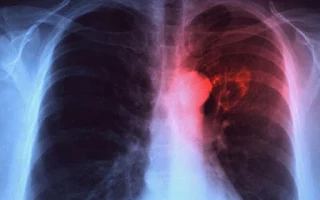

Este año, el Servicio Nacional de Salud (SNS) recibió de la Dirección General de Presupuesto RD$88.9 millones para la prevención, diagnóstico y tratamiento oportuno de la tuberculosis en las Regionales de Salud Metropolitana, Norcentral y Este, donde se presenta la mayor incidencia de casos.

La directora de Asistencia a la Red, doctora Rubelina Santos, indicó que el SNS ha incluido entre sus prioridades la atención a la tuberculosis, consciente de la importancia de la prestación de servicios de salud en la prevención y control de la enfermedad.

En ese sentido, indicó que se están implementando los Programas Presupuestarios Orientados a Resultados, basados en actividades comunitarias con estrategias de probada eficacia, a través de las cuales se busca disminuir la incidencia de casos de tuberculosis y perdidos durante el seguimiento.

Estas estrategias son la aplicación del Tratamiento Directamente Observado al Domiciliario a pacientes con riesgo de baja adherencia y dificultad de acceso a los servicios de salud, y la aplicación del Paquete de Apoyo a la Salud Mental en todos los pacientes diagnosticados.